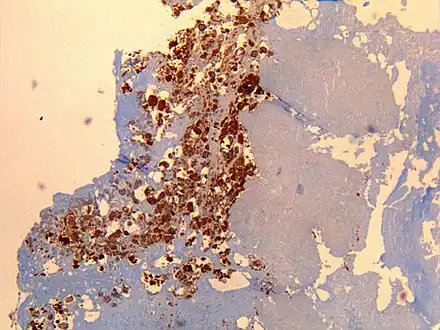

| Immunohistochemistry showing C. burnetii in a heart valve of a 60-year-old with Q fever endocarditis: Monoclonal antibodies and hematoxylin were used for staining; original magnification is ×50. | |